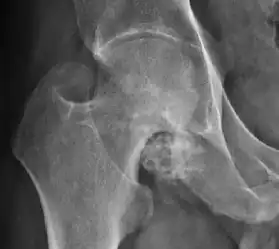

Plain radiography allows us to categorize the hip as normal or dysplastic or with impingement signs (pincer, cam, or a combination of both). Besides these, pathologic processes like osteoarthritis, inflammatory diseases, infection, or tumors can also be identified (Figure 1).[1]

Figure 1.

-

Radiography in normal hip -

X-ray in pincer impingement type of hip dysplasia -

X-ray of cam -

Hip in osteoarthritis -

Septic arthritis

X-ray in pediatrics